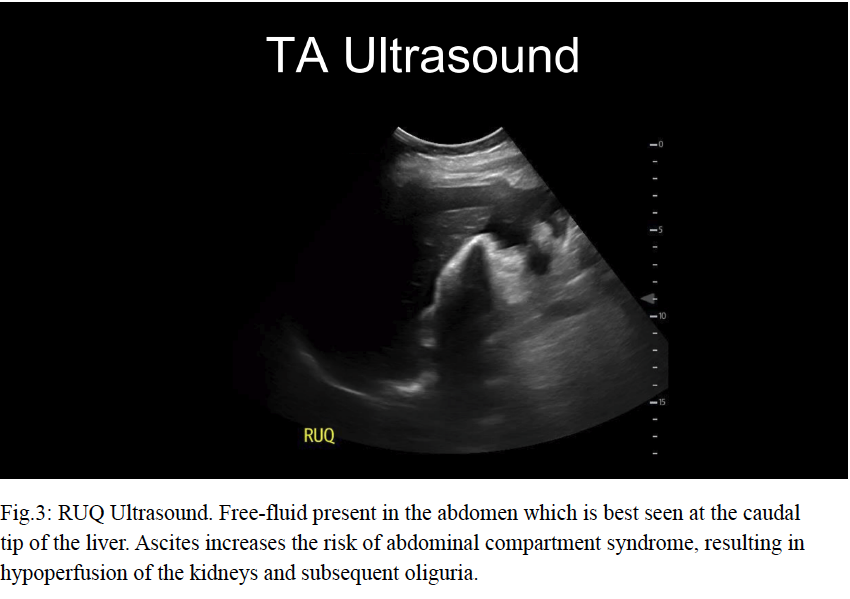

Let’s dive into some POCUS findings. Clinically, there are varying degrees of OHSS. The severe form has pretty profound clinical and sonographic findings. Severe abdominal pain is accompanied by a large amount of free fluid on abdominopelvic assessment. The ovaries are enlarged >12cm in diameter and contain numerous large thin-walled cysts which obliterate the normal ovarian parenchyma. Evaluation of the blood flow to the ovaries is crucial in these patients due to their increased risk for ovarian torsion.